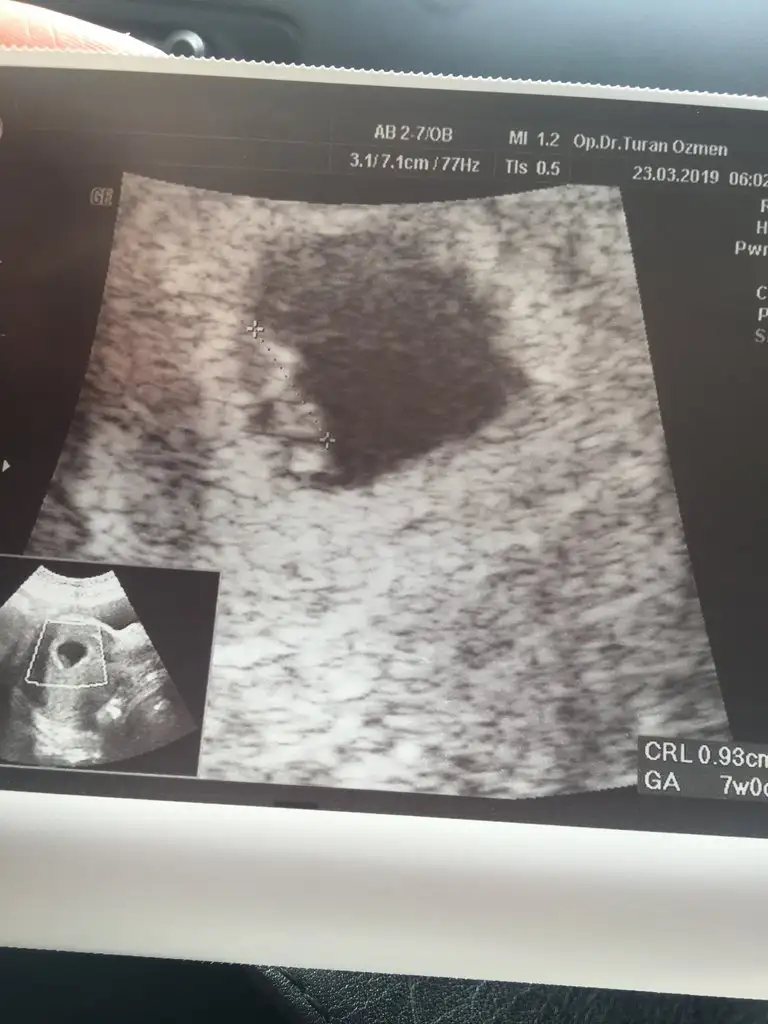

Benimde bugün kontrolüm vardı minik fasülyemi gördük kalp atışlarını duyduk çok şükür analiz yapan arkadaşlar dkda130 atıyordu ve ultrason görüntüsüne de bir bakıversinler ☺

Eki Görüntüle 2254218